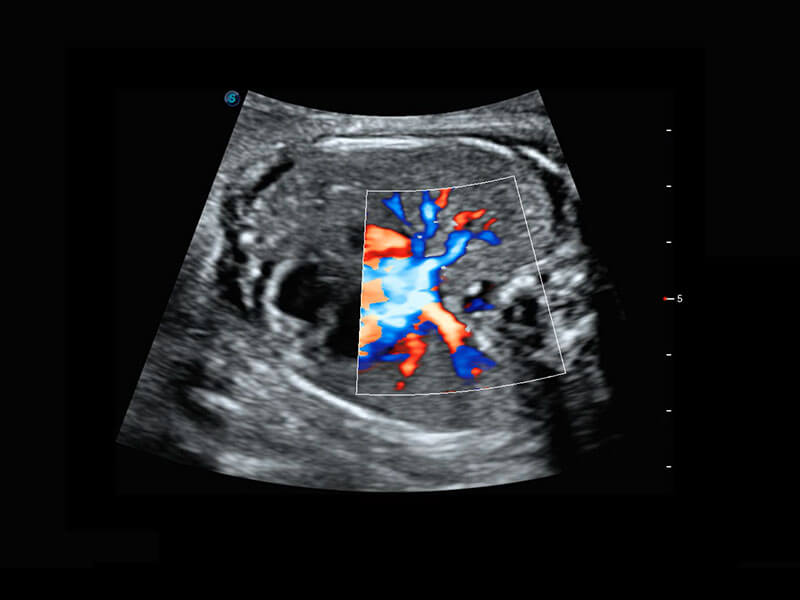

胎儿体循环

P60搭载一系列胎儿心脏成像技术,实现精细的胎儿心脏评估。

四腔切面

四腔心血流